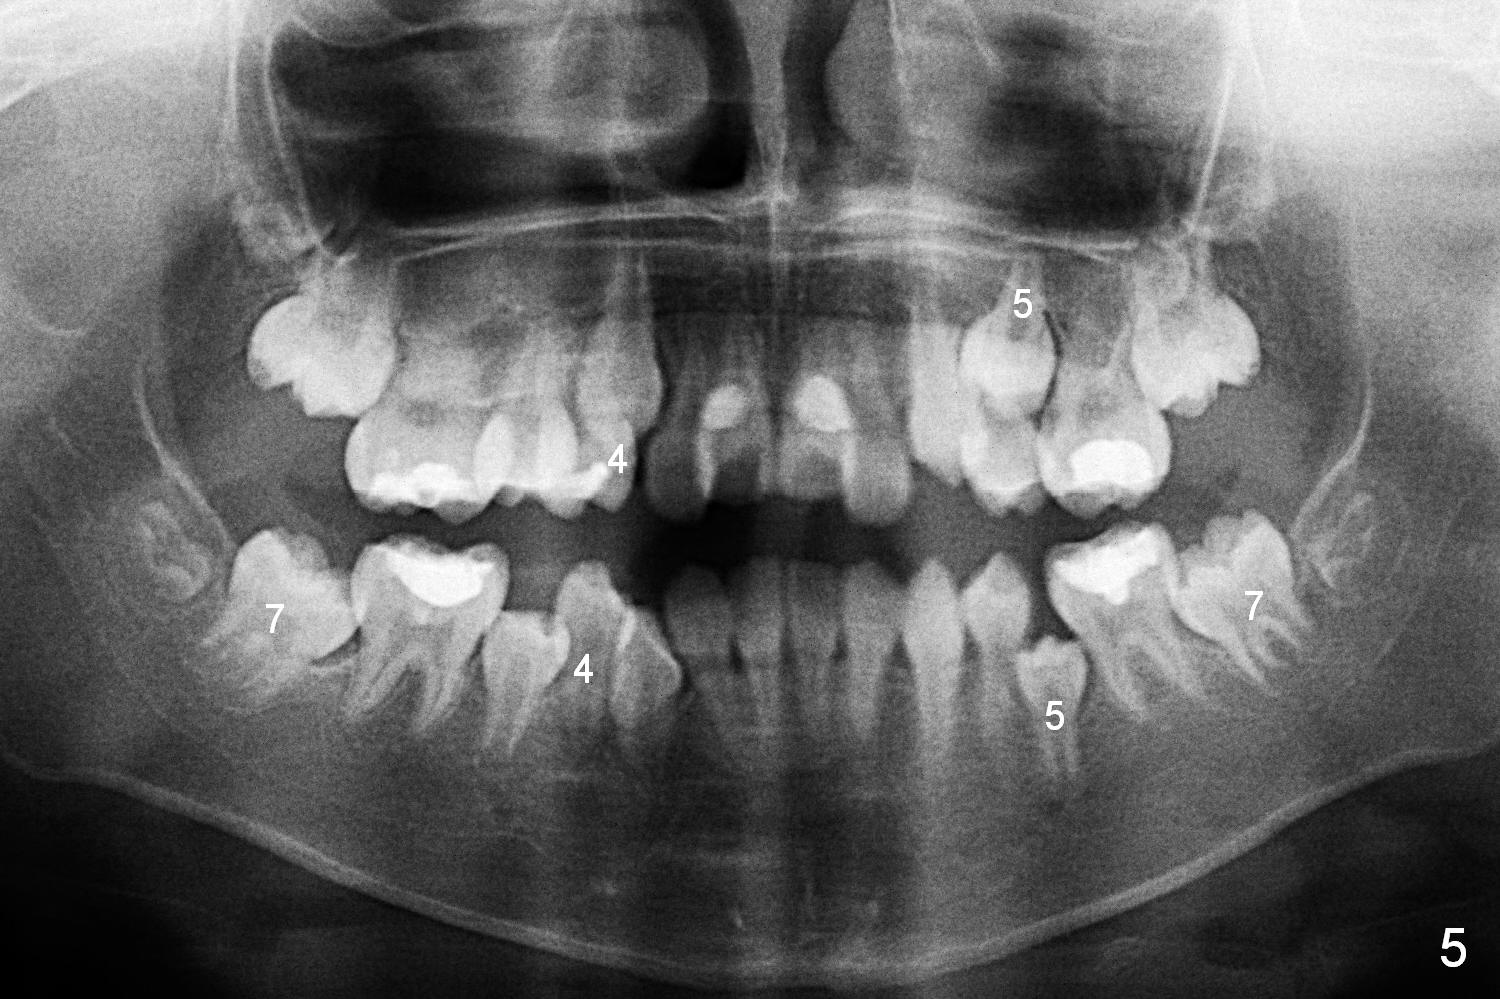

A 10-year-old girl with history of hyper-thyroidism has severe Class I malocclusion. She is ready for treatment. There is mild lip strain (suggesting anterior tooth protrusion, Fig.1,3). The facial and dental midlines coincide (Fig.2). Severe crowding is evident. Extraction orthodontics is indicated, either next to the most crowded areas (UR, LR4, Fig.6) or impacted ones (UL, LL5, Fig.10,11 (mirror view)).

When L3s is repositioned normally, try to mesialize the posterior teeth so that L7s have space to erupt (Fig.5).